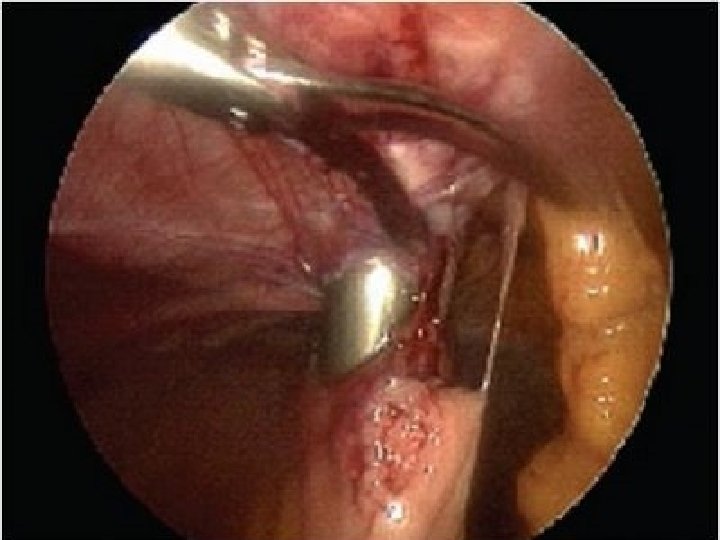

Diagnóstico �Laparoscopia y biopsia dirigida

Sutton CJ, Ewen SP, Whitelaw N, Haines P, Prospective randomized doubleblind controlled trial of laser laparoscopy in the treatment of pelvic pain associated with minimal, mild, and moderate endometriosis. Fertil Steril, 1994; 64: 696 -700. 1 solo estudio aleatorizado: 74 pacientes estadíos I, III sometidas a ablación implantes con laser, lisis adherencial y LUNA (laparoscopic uterine nerve ablation: Ablación de las fibras sensitivas parasimpáticas que van al cervix y de las fibras simpáticas que van al cuerpo uterino). - Mejoría 62, 5% en pacientes tratadas - Mejoría 22, 6% en pacientes NO tratadas Metodologicamente el problema es que combina diferentes medidas terapeúticas, por lo que no sabemos el valor individual de cada procedimiento.

Tratamiento quirúrgico de la endometriosis asociado a la esterilidad

� La quistectomía laparoscópica de los endometriomas mayores de 4 cm mejora la fecundidad en mayor medida que el drenaje y coagulación (NE: Ia-A). � Por otro lado, existe un riesgo de reducción de la función ovárica en toda cirugía del endometrioma ovárico, por lo que la exéresis de la cápsula debe realizarse de forma cuidadosa.